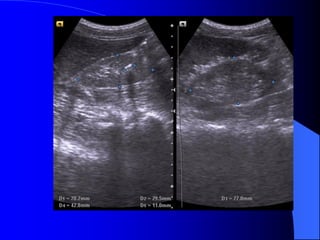

* SA: tháûn nhoí, nhu mä teo, båì läöi loîm. Nhu mä tháûn håi tàng

ám khäng phán biãût tuíy voí tháûn. ÆÏ âoüng måî xoang tháûn

thæåìng gàûp (Lipomatose).

* NÂTM: tháûn nhoí khäng cán

xæïng bãn âäúi diãûn, båì läöi loîm,

nhu mä moíng khäng âãöu ngang

våïi mæïc âaìi tháûn, âaìi tháûn naìy

coï hçnh chuìy.